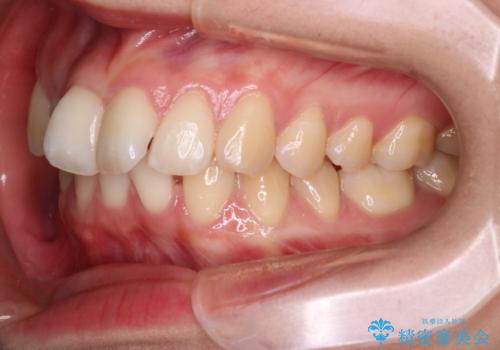

- 患者様は、上下の噛み合わせのバランスが悪く、特に上顎の前歯の突出を気にされて来院されました。診査の結果、下顎の歯並びに合わせて上顎を後方へ移動させる必要があると判断し、上顎の小臼歯2本を抜歯することを提案しました。目立たない矯正を希望されたため、**インビザライン(マウスピース矯正)**を選択。計画的にスペースを作りながら、バランスの取れた歯並びを目指しました。

治療はまず、上顎の小臼歯を2本抜歯し、そのスペースを利用して前歯を後方へ移動させました。インビザラインはアタッチメントを併用し、より効率的に歯を動かせるよう調整。定期的なチェックとアライナーの交換を続け、約3年かけて理想的な歯並びと噛み合わせを実現しました。治療後はリテーナーを使用し、安定した状態を維持。患者様からは「口元がスッキリし、横顔の印象も変わった」と嬉しいお声をいただきました。